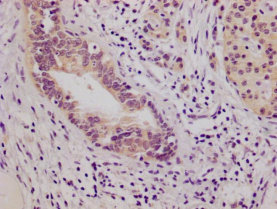

IHC image of CSB-MA614961A0m diluted at 1:100 and staining in paraffin-embedded human pancreatic cancer tissue performed on a Leica BondTM system. After dewaxing and hydration, antigen retrieval was mediated by high pressure in a citrate buffer (pH 6.0). Section was blocked with 10% normal goat serum 30min at 37℃. Then primary antibody (1% BSA) was incubated at 4°C overnight. The primary is detected by a Goat anti-mouse IgG labeled by HRP and visualized using 0.05% DAB.